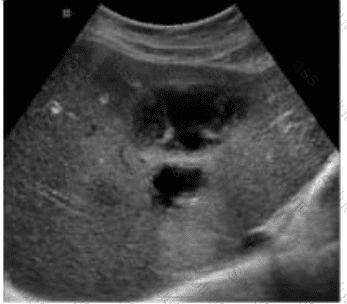

Which condition of the transplant kidney is indicated by the arrows on these images?